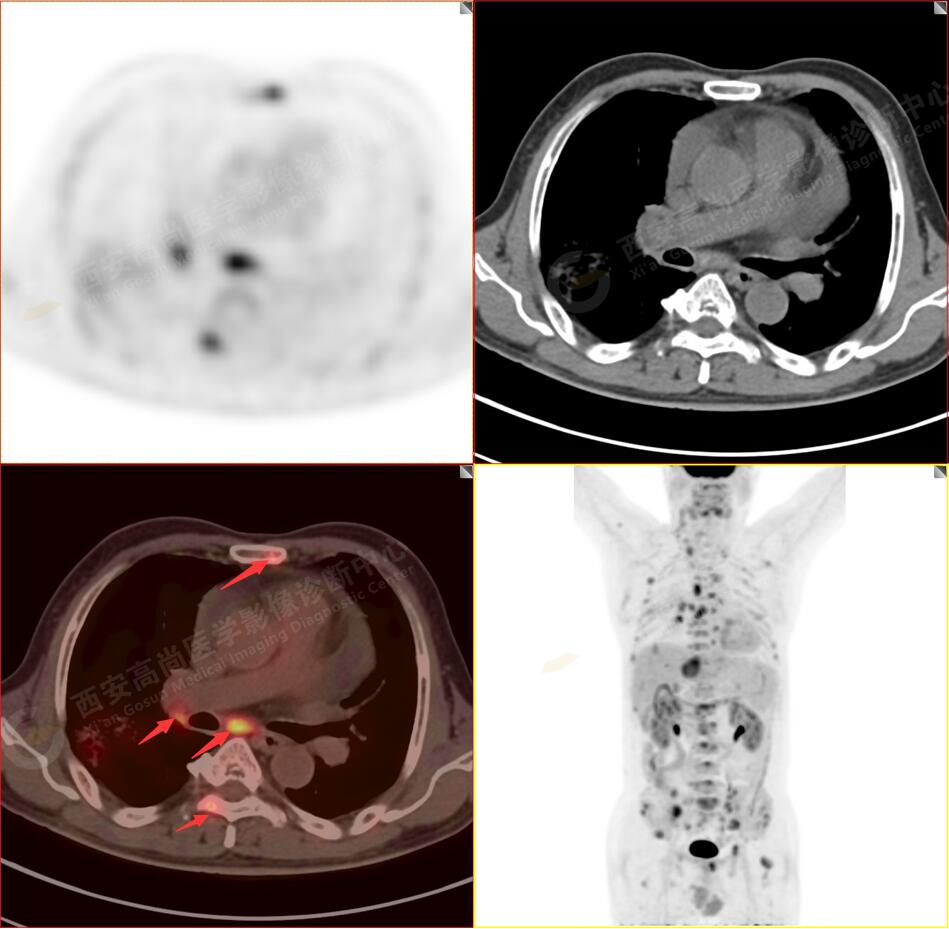

2.以下為全身多發(fā)轉移灶

3.右側頸部(Ⅱ-Ⅴ區(qū))、右側腋窩區(qū)、右側肺門及縱隔(1R、1L、2、4、6、7組)、肝門區(qū)多發(fā)腫大淋巴結,呈不同程度異常增高,均考慮為淋巴結轉移。